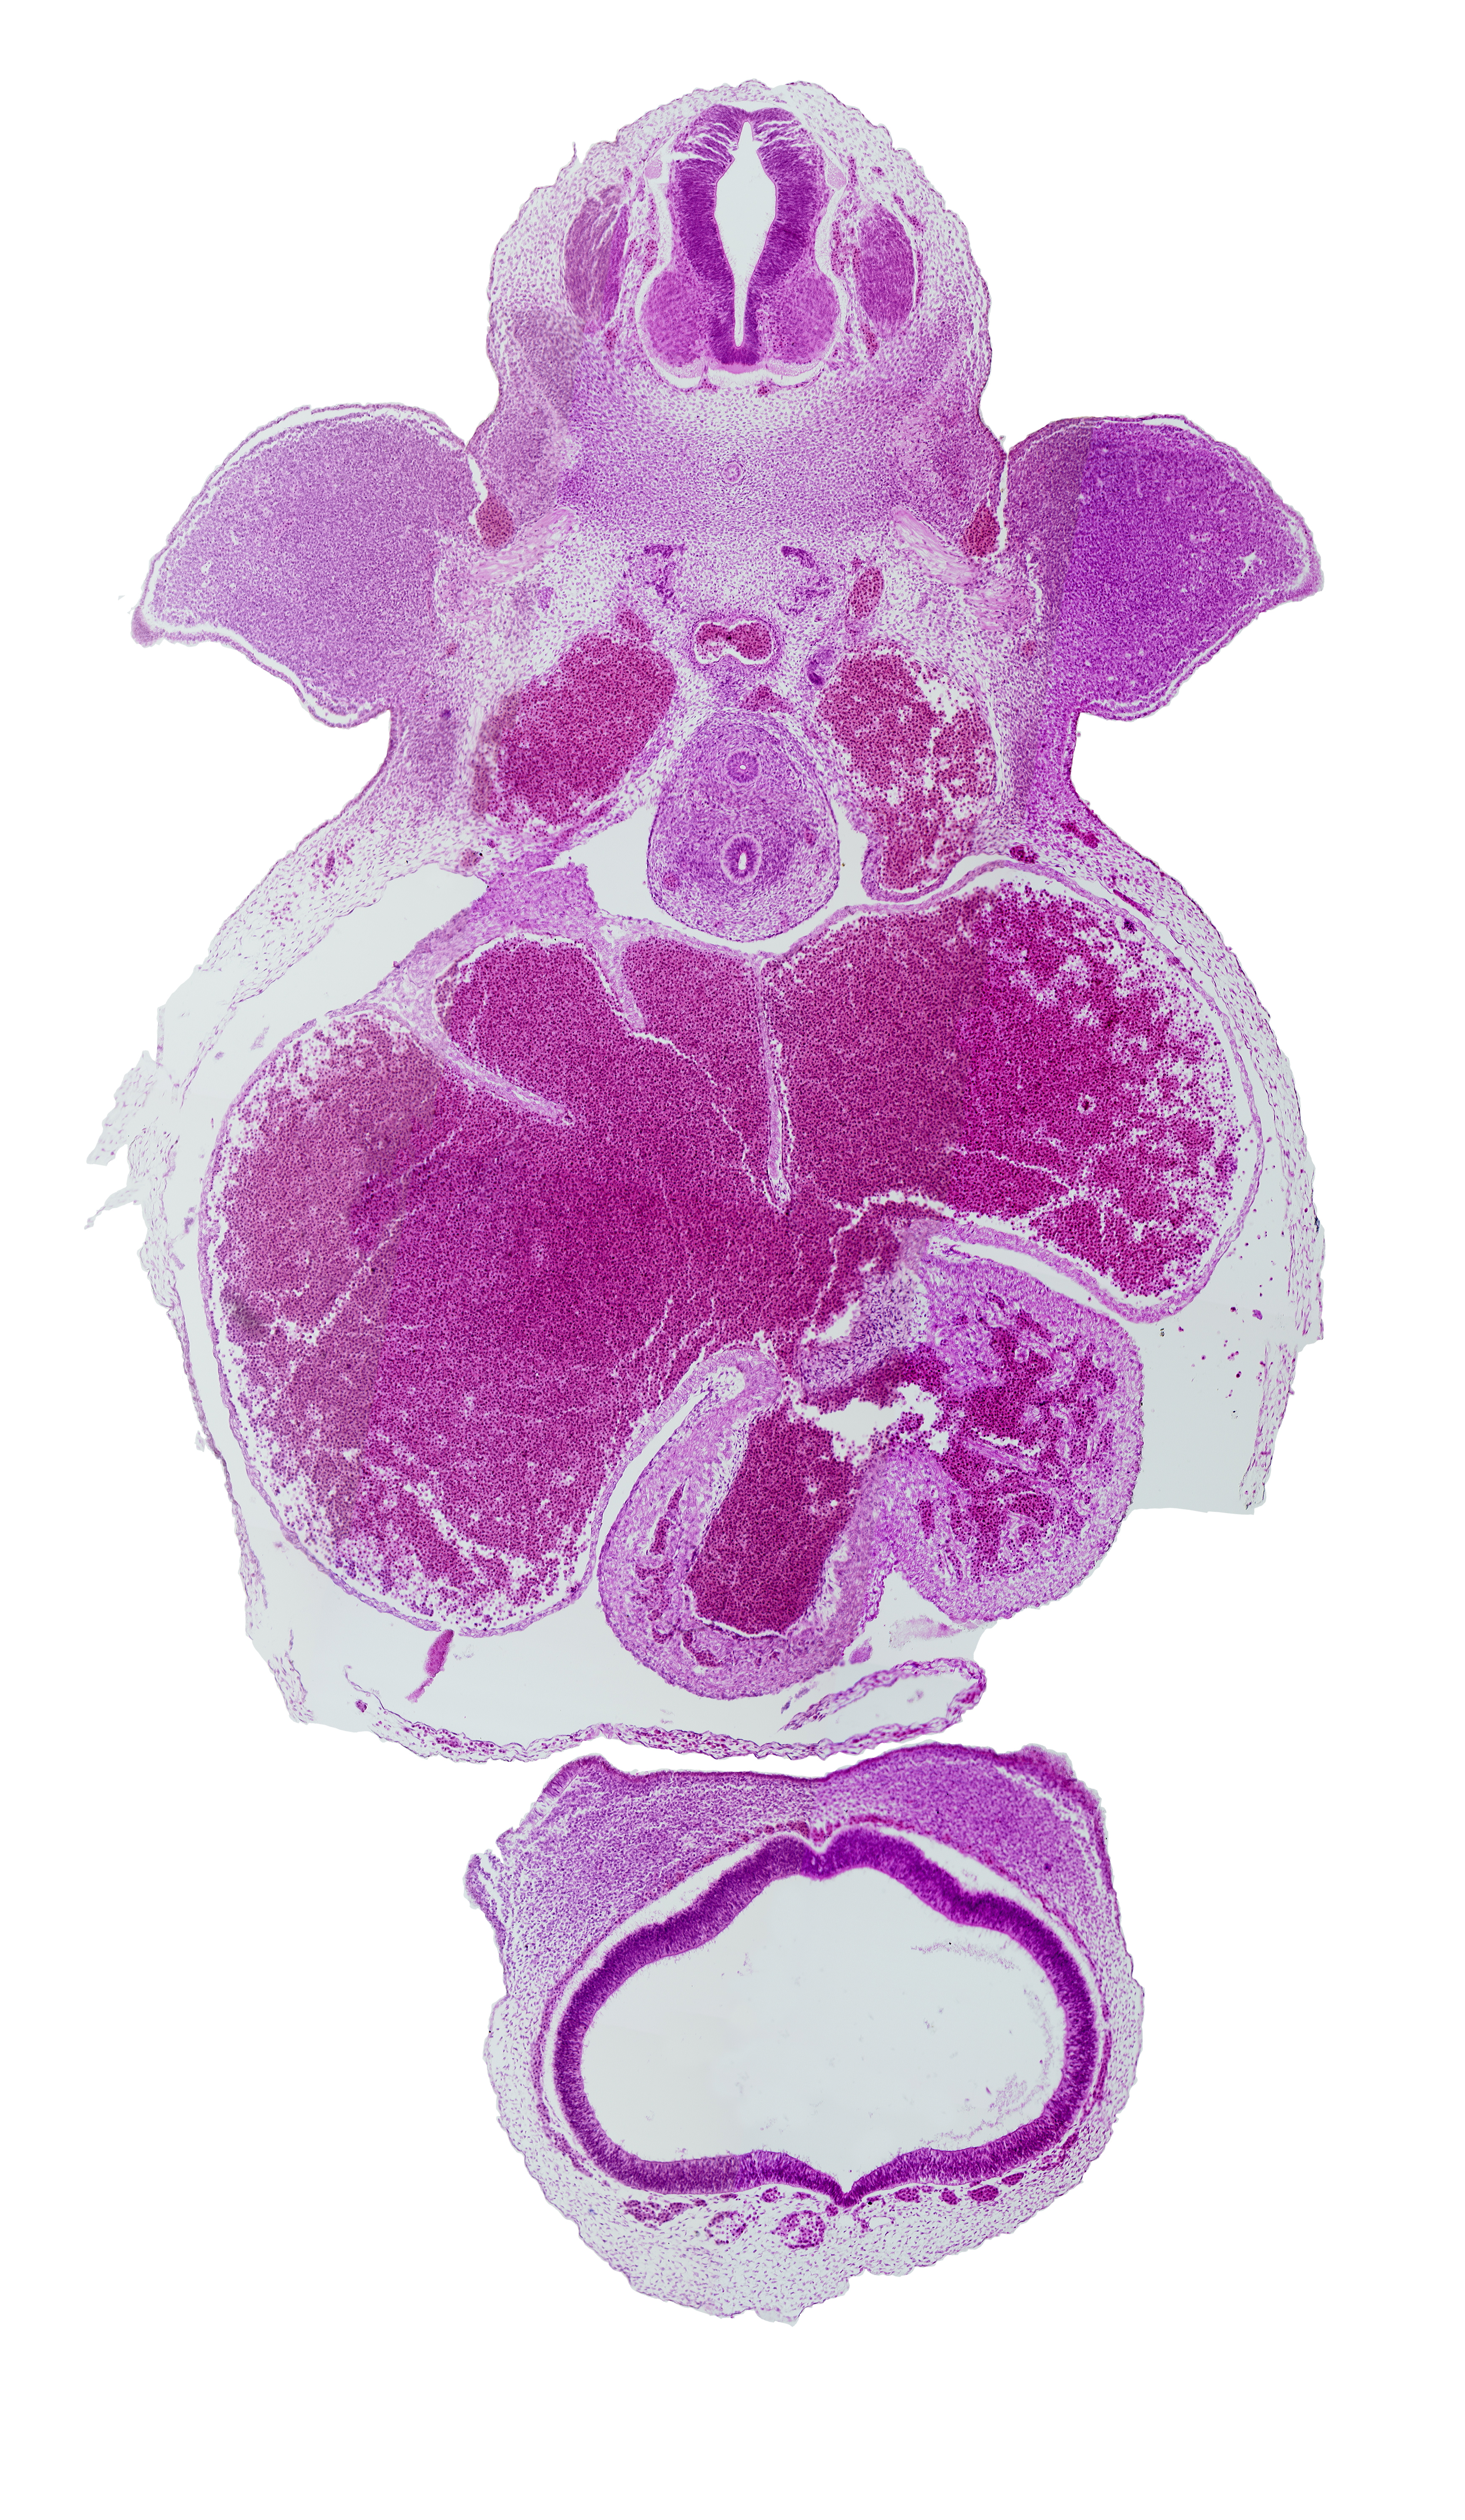

Carnegie Embryo #721 | Location: 12-01-03

Keywords: C-7 spinal ganglion, apical epidermal ridge, cephalic edge of nasal prominences, esophagus, hippocampus, junction of cardinal vein and common cardinal vein, junction of dorsal aortas, left venous valve, left ventricle, musculi pectinati, precardinal vein (internal jugular vein), primary interatrial foramen (foramen primum), primary interatrial septum (septum primum), right atrium, right venous valve, sinu-atrial foramen, sinus venosus, telencephalon medium, trachea

Source: The Virtual Human Embryo.